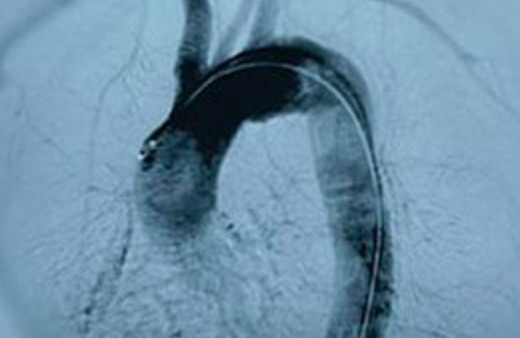

Aort Anevrizması